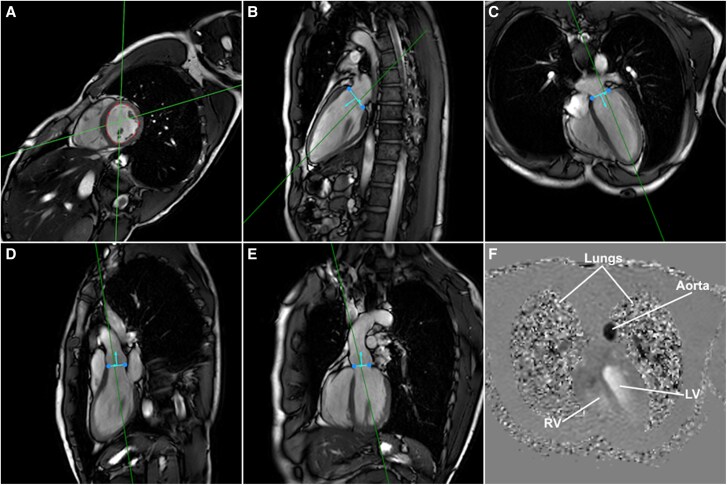

Aims: 4D flow magnetic resonance imaging (MRI) has enabled evaluation of intracardiac flow dynamics by particle tracing for visualizing and quantifying complex flow patterns. The aim of this study was to assess the impact of respiratory motion compensation on 4D flow MRI-based left ventricular four-component particle tracing, valve tracking, and haemodynamics.

Methods and results: In this prospective cohort study, 4D flow MRI with and without respiratory motion compensation was performed in 15 healthy volunteers. Intracardiac particle tracing considered four components: direct flow, delayed ejection flow (DEF), retained inflow (RI), and residual volume. Data quality was assessed by comparing DEF and RI components. Particle tracing, valve tracking, kinetic energy (KE), and vorticity were compared between scan methods. Paired sample t-tests and intraclass correlation analysis were performed with an alpha of 0.05. DEF, RI, ejection fraction, and stroke volume were different between scan methods. Five participants showed DEF-RI mismatch > 10%. After excluding these, differences in flow fractions were non-significant. Differences in stroke volume, ejection fraction, and valvular flow mismatch between scan methods remained. Valve tracking was comparable between scan methods and correlated well with particle tracing. Absolute mismatch between particle tracing- and valve tracking-based mitral flow, and KE and vorticity at A-peak, was higher for non-compensated MRI.

Conclusion: Respiratory motion compensation can improve accuracy of intracardiac particle tracing based on 4D flow MRI by decreasing mismatch to retrospective valve tracking. For intracardiac particle tracing, respiratory motion compensation is advised. Robust data quality assessment for particle tracing-based analyses is equally crucial.